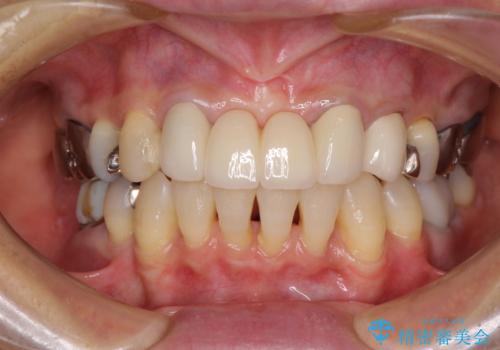

- 矯正治療を行った歯科医院で装着した前歯の仮歯が不快とのことで来院された患者様です。

仮歯自体はとても綺麗でしたが、2本の歯が欠損している部分に上唇小帯が入り込んでいたため、歯肉形成を行った上で仮歯を調整し、オールセラミックブリッジを装着することとしました。

他にも治療が必要な歯があったため、合わせてセラミッククラウンやセラミックインレーで治療することとしました。

上唇小帯を切除したことで、ブリッジのダミー部分に触れて腫れていた歯肉は健全な状態になりました。

隙間もなくなったことで話す際の空気の漏れや、ものが挟まることもなくなりました。